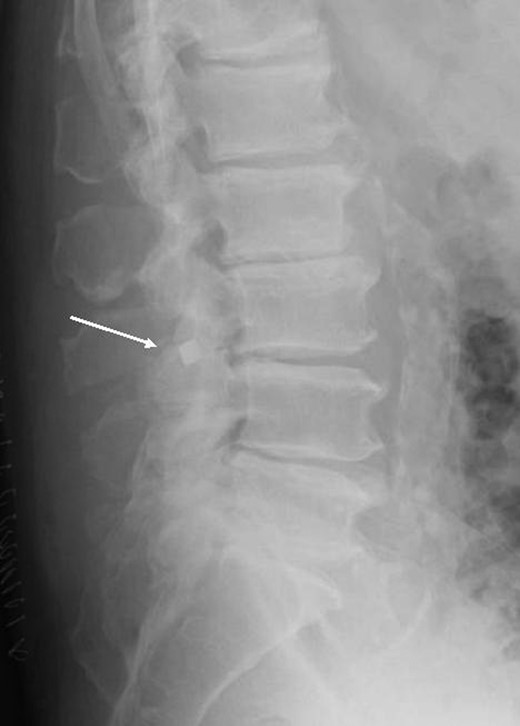

Postoperative Anterior-Posterior and lateral (Figs 1 and 2) radiographs of the lumbo-sacral spine revealed a radio-opaque foreign body on the right side of the spinal canal. The patient returned to theatre 3 days following the original operation for wound exploration. The foreign body was found to be lying in the spinal canal on the right side with an associated small dural tear. The object was identified as a broken metal tip and traced to an osteotome used in the primary procedure.

The most plausible explanation for this complication is that during the release of the hypertrophied facet joint, the osteotome tip broke. What is particularly concerning is the fact that although the approach was on the left side, the broken tip was able to traverse the midline and settle adjacent to the spinal canal on the right, tearing the dura in the process.